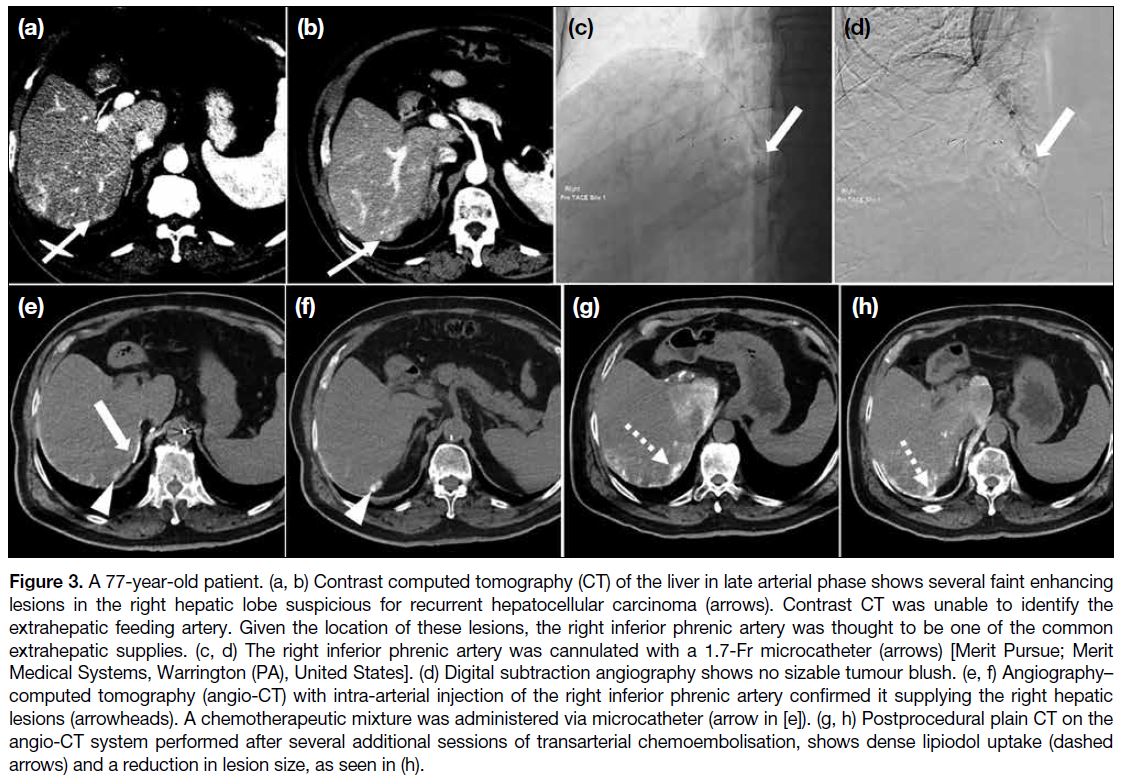

Figure 3. A 77-year-old patient. (a, b) Contrast computed tomography (CT) of the liver in late arterial phase shows several faint enhancing

lesions in the right hepatic lobe suspicious for recurrent hepatocellular carcinoma (arrows). Contrast CT was unable to identify the

extrahepatic feeding artery. Given the location of these lesions, the right inferior phrenic artery was thought to be one of the common

extrahepatic supplies. (c, d) The right inferior phrenic artery was cannulated with a 1.7-Fr microcatheter (arrows) [Merit Pursue; Merit

Medical Systems, Warrington (PA), United States]. (d) Digital subtraction angiography shows no sizable tumour blush. (e, f) Angiography–computed tomography (angio-CT) with intra-arterial injection of the right inferior phrenic artery confirmed it supplying the right hepatic

lesions (arrowheads). A chemotherapeutic mixture was administered via microcatheter (arrow in [e]). (g, h) Postprocedural plain CT on the

angio-CT system performed after several additional sessions of transarterial chemoembolisation, shows dense lipiodol uptake (dashed

arrows) and a reduction in lesion size, as seen in (h).